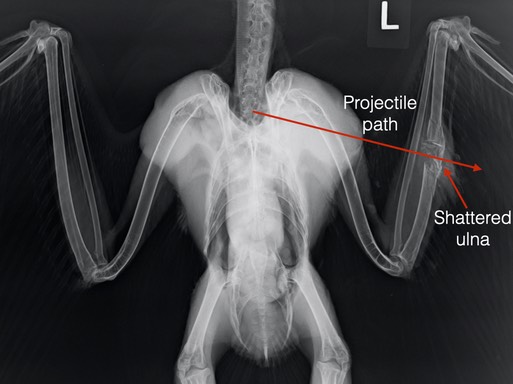

Merlin 20-587

A female Merlin was found on the ground in a trailer park in Irrigon, Oregon. A Morrow County deputy indicated the small falcon had been shot. Her wounds were consistent with a gunshot injury. There was a tiny entrance wound at the top of her right shoulder. There was a much larger exit wound below her right elbow. The projectile traveled parallel to the humerus and didn’t break any bones, though there is some asymmetry in the right elbow. We are hopeful the wing will heal and the bird will be releasable. You can see from the radiograph that she also is in excellent physical condition.